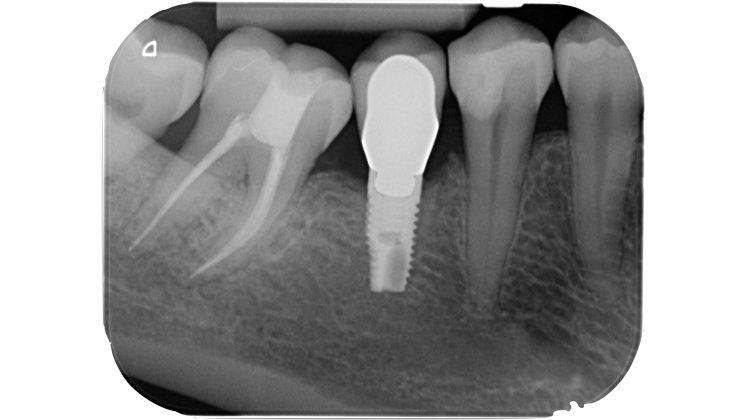

Devono essere valutate con molta attenzione la posizione dell’elemento in arcata e la sua inclinazione (Figure 6-7), l’entità e la posizione del processo carioso se presente, gli eventuali restauri posizionati sul dente e i rapporti con il parodonto: tutte queste considerazioni permetteranno al clinico di capire innanzitutto la mantenibilità e la possibilità di isolare mediante diga di gomma il dente. L’interpretazione degli esami radiografici consentirà inoltre di valutare alcuni parametri preoperatori di notevole importanza:

- presenza di pregresse terapie canalari e valutazione della qualità delle stesse;

Un’attenta analisi di questi dati clinici e radiografici consentirà al clinico di ridurre notevolmente il rischio di errori grossolani in questa delicata fase del trattamento.